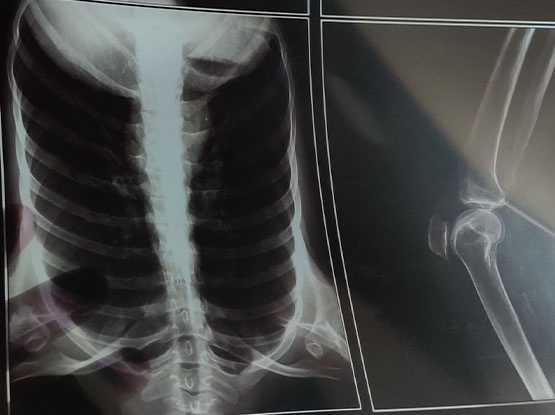

Medical Film for FUJI Printer Dry Film Laser Film Thermal Film

| Model NO. | medical film |